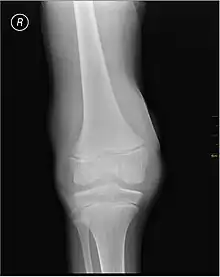

X-ray of Hemarthrosis